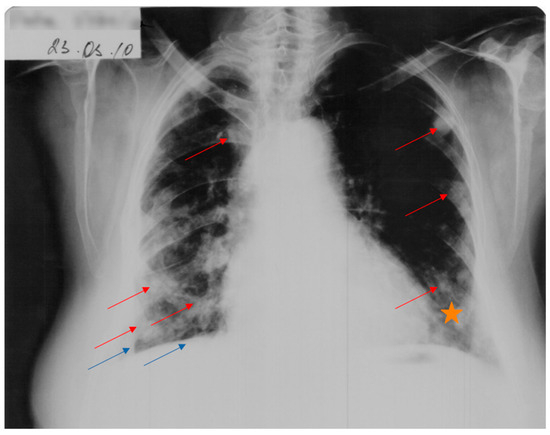

A favorable evolution of the cysts under antiparasitic treatment was observed in October 2009 and March 2010 (Figure 4).

Figure 4. Cardio-thoracic radiograph showing a favorable evolution of the cysts (red arrows) and diffuse para-cardiac opacity (star) under antiparasitic treatment. Persistence of right-lung retraction can be observed (blue arrows).